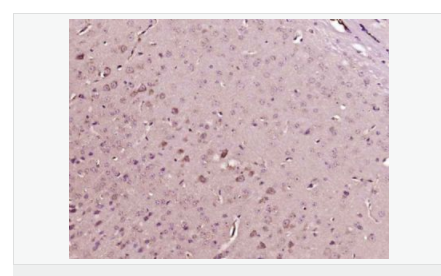

交叉反應(yīng):Human,Mouse,Rat(predicted:Phosphotyrosine) 推薦應(yīng)用:IHC-P,IHC-F,ICC,IF

| 產(chǎn)品應(yīng)用 | IHC-P=1:100-500 IHC-F=1:100-500 ICC=1:100-500 IF=1:100-500 (石蠟切片需做抗原修復(fù)) not yet tested in other applications. optimal dilutions/concentrations should be determined by the end user. |